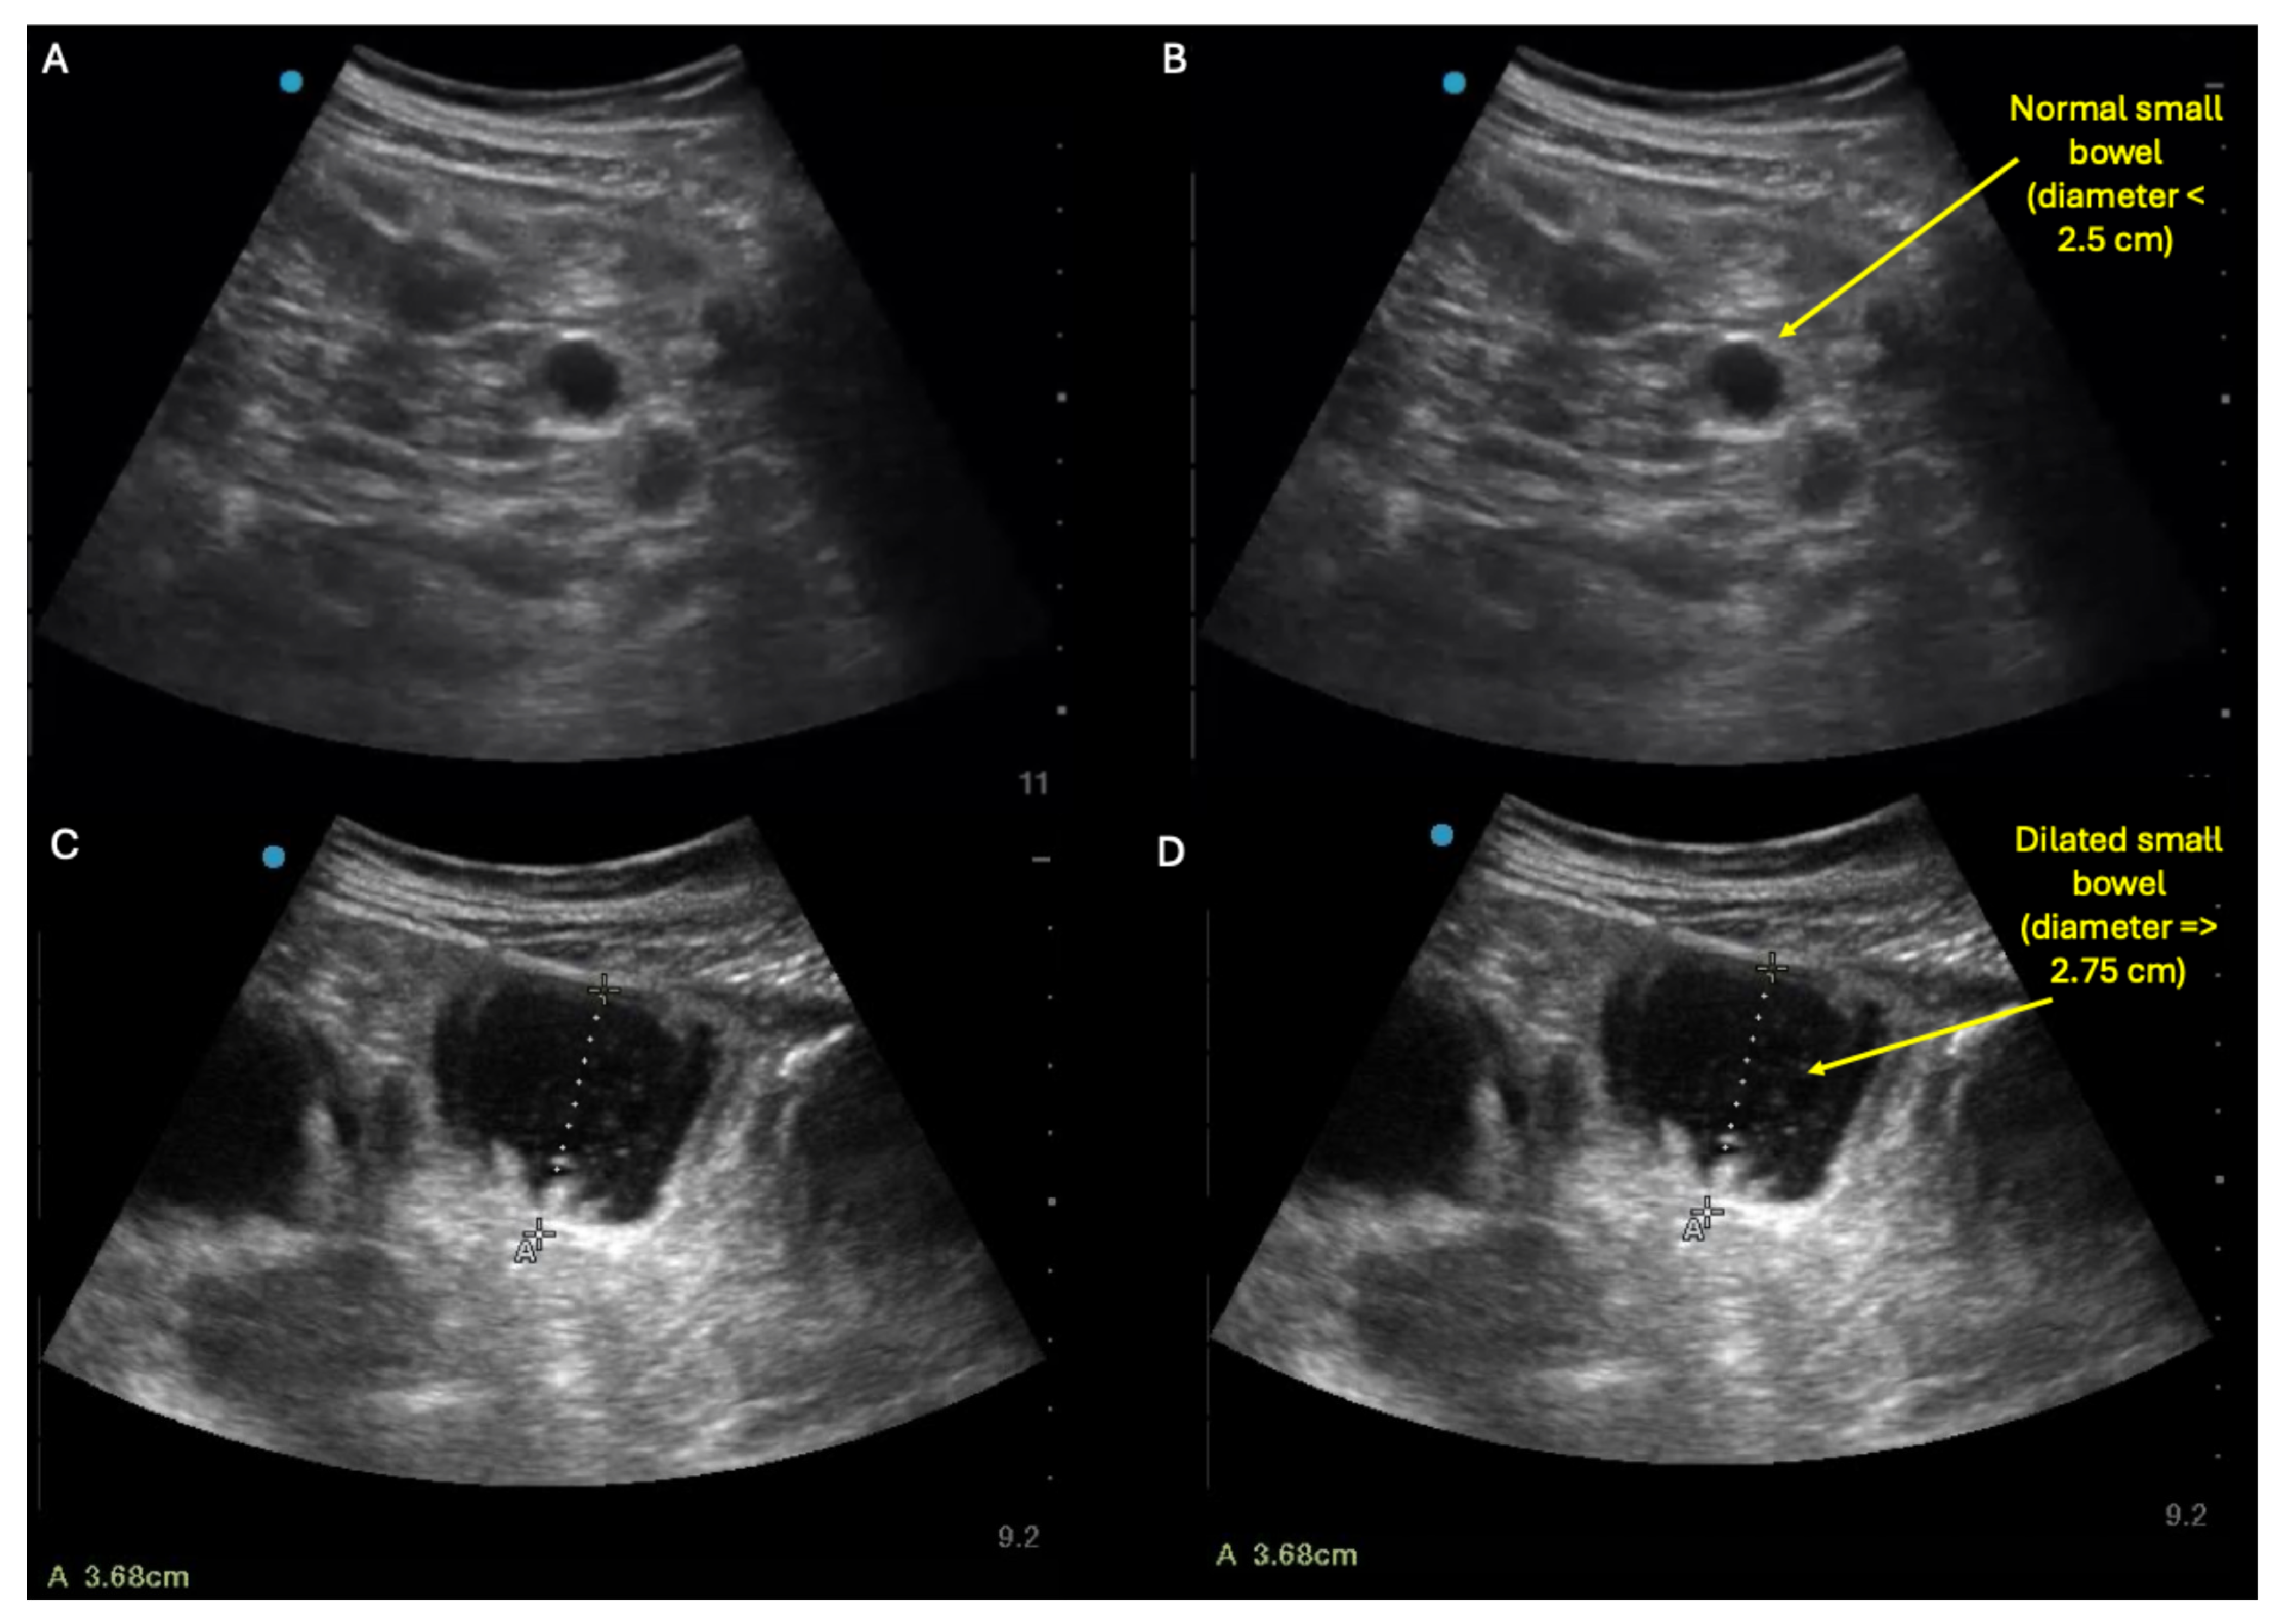

Similarly to small bowel ileus, small bowel obstruction (SBO) on ultrasound will appear as dilated loops of bowel, defined as small bowel diameter ≥ 2.75 cm [11,12,13]. But in contrast to ileus, SBO may also show decompressed small bowel loops in the same abdomen. Thus, the characteristic sonographic finding of small bowel obstruction is concurrent visualization in the same abdomen of both (a) small, decompressed (≤2.5 cm diameter) loops of small bowel (top panel: A,B) and (b) dilated (≥2.75 cm diameter) loops of small bowel lacking peristalsis (bottom panel: C,D) (see also Supplementary Video S4 for examples of these dynamic findings). However, in some cases of SBO, the decompressed loops may not be visualizable with ultrasound, making it difficult to differentiate SBO versus ileus using ultrasound alone. In such cases where ultrasound reveals diffusely dilated loops of small bowel with no decompressed loops and SBO is still suspected, adjunctive imaging such as X-ray and/or CT scan can be pursued.